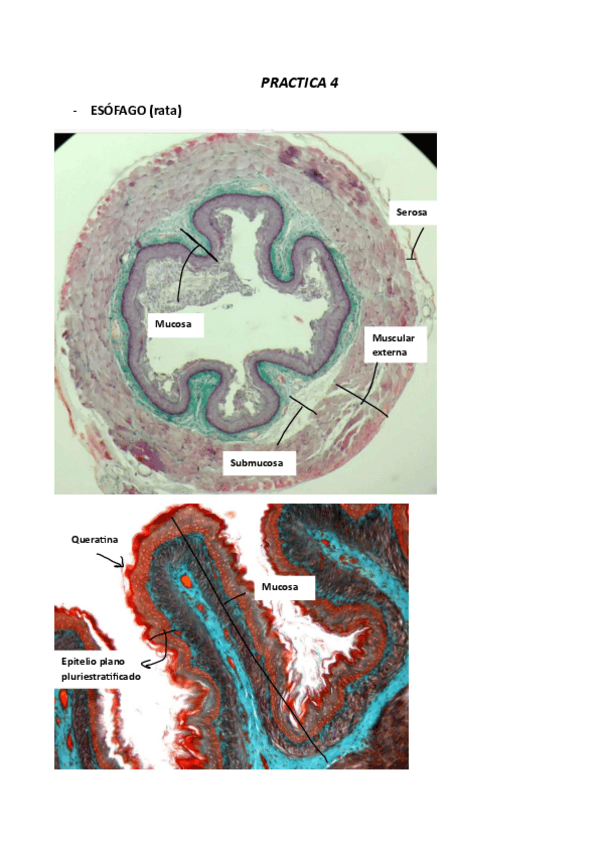

PRACTICAS HISTOLOGIA

PRACTICA-4.pdf